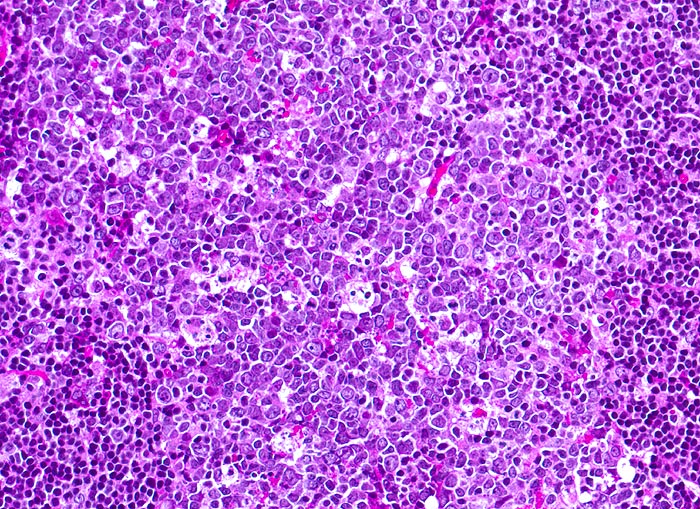

infektiöse Mononukleose: follikuläre Hyperplasie

Ausschnitt aus einem Lymphfollikel mit grossem Keimzentrum. Im Keimzentrum finden sich neben kleinen Zentrozyten und grösseren Zentroblasten mehrere Sternhimmelmakrophagen mit phagozytierten Kerntrümmern.

Tonsillektomie bei einem Studenten mit Angina, Lymphknotenschwellungen und einer Lymphozytose im Blut.